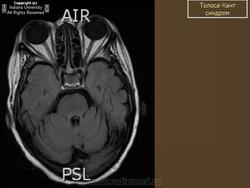

Синдром Толоза - Ханта: неврологический хамелеон

Синдром Толоза - Ханта (СТХ, болезненная офтальмоплегия, синдром верхней глазничной щели) впервые описан испанским неврологом E. Tolosa в 1954 г. и дополнен английским врачом W. Hunt в 1961 г. [6, 15]. Эта патология проявляется поражением структур, проходящих через верхнюю глазничную щель (глазничная артерия и вена, отводящий, блоковый, глазодвигательный нервы, первая ветвь тройничного нерва), и прилегающего к ней кавернозного синуса. Клиническая картина СТХ характеризуется болями чаще в области орбиты, диплопией, экзофтальмом и хемозом, которые проявляются в различных сочетаниях и бывают разной степени выраженности [7, 8, 13]. Практика показывает, что сходные клинические признаки наблюдаются при широком круге неврологических и соматических заболеваний: бактериальном, вирусном и грибковом воспалении наружной стенки кавернозного синуса или мозговых оболочек; первичных либо вторичных опухолях мозга и орбиты; сосудистых мальформациях и диссекциях ветвей внутренней сонной артерии; тромбозе, лимфоме, эпидермоидных кистах кавернозного синуса; орбитальном миозите, саркоидозе, гранулематозе Вегенера, некоторых заболеваниях крови, офтальмической мигрени и др. [1-3, 5, 12, 14].

Таким образом, в основе формирования СТХ лежат различные причины, которые определяют многоликий характер заболевания. В природе подобный аналог разнообразия назван хамелеоном. За последние годы достигнут несомненный прогресс в понимании механизмов развития этого заболевания. Cогласно критериям, разработанным International Headache Society (2004), диагноз СТХ обоснован в случаях выявления гранулемы наружной стенки кавернозного синуса при магнитно-резонансной томографии (МРТ) головного мозга либо при проведении биопсии [10]. При отсутствии изменений на МРТ более правомочен термин «синдром верхней глазничной щели», и в этих случаях пациенты нуждаются в динамическом наблюдении.

В последние годы в диагностике СТХ большую роль отводят методам нейровизуализации, так как проведение биопсии транссфеноидальным доступом обычно ограничено. T. Ozawa et al. [11] предложили МРТ-критерий СТХ: наличие в стенке кавернозного синуса патологической ткани, изоинтенсивной в Т1w-режиме и изогипоинтенсивной в Т2w-режиме. По данным La L. Mantia et al. [10], воспалительная инфильтрация или гранулемы в области кавернозного синуса при МРТ обнаружены в 44 (35 %) из 124 случаев СТХ. T.L. Haque et al. при МРТ выявляли маленькие очаги, примыкающие к краниальным нервам без распространения на кавернозный синус. При проведении МРТ в динамике после приема глюкокортикоидов авторы обнаруживали полное исчезновение очагов, что позволяет предположить их гранулематозный характер [4].